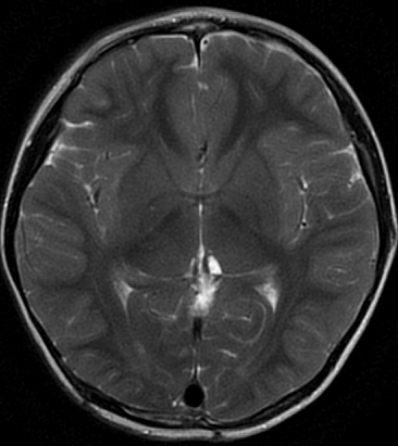

3岁男性患儿,间断头痛两个月入院,头部MR检查结果提示松果体区占位病变并梗阻性脑积水。

头部MR检查T2水平位显示松果体区囊实性占位病变,同时表现侧脑室及三脑室轻度扩张。

矢状位MR可见松果体区占位病变。